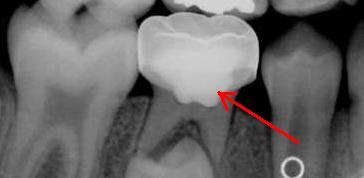

The pulpotomy procedure is referred to by many dentists as a “baby root canal”. The reason is, much like a root canal, you remove the affected or inflamed portion of the pulp tissue, and treat any remaining bacteria in the pulp space with a medicinal solution. Once this is completed, the pulp space where the nerve tissue was once located is then filled-in with an intermediate restorative material (IRM) to keep the tooth from rejecting itself; preserving the natural space for the adult tooth to come in normally.

After such procedures, it is recommended to have this tooth monitored at your semi-annual checkups to make sure no internal resorption or signs of complications are present. The stainless steel crown will typically reabsorb and fall out naturally like a normal functioning baby tooth would. This procedure is very important for maintaining normal spacing and development of a child’s mouth.